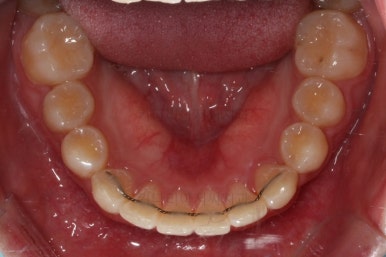

마무리 때의 모습입니다.

임시 개념으로 치아 사이즈를 키운건데 환자분은 만족하시나봐요.

보통 올세라믹, 라미네이트 등 보철치료는 성인이 되어서 해야해서 이래나 저래나 이정도에서 만족하기로 했습니다.

치아는 매우 가지런해졌고 뾰족하던 앞니의 형태도 좋아졌어요.

매복되어 있던 송곳니도 잘 나왔고 과개교합도 물론 개선이 되었습니다.